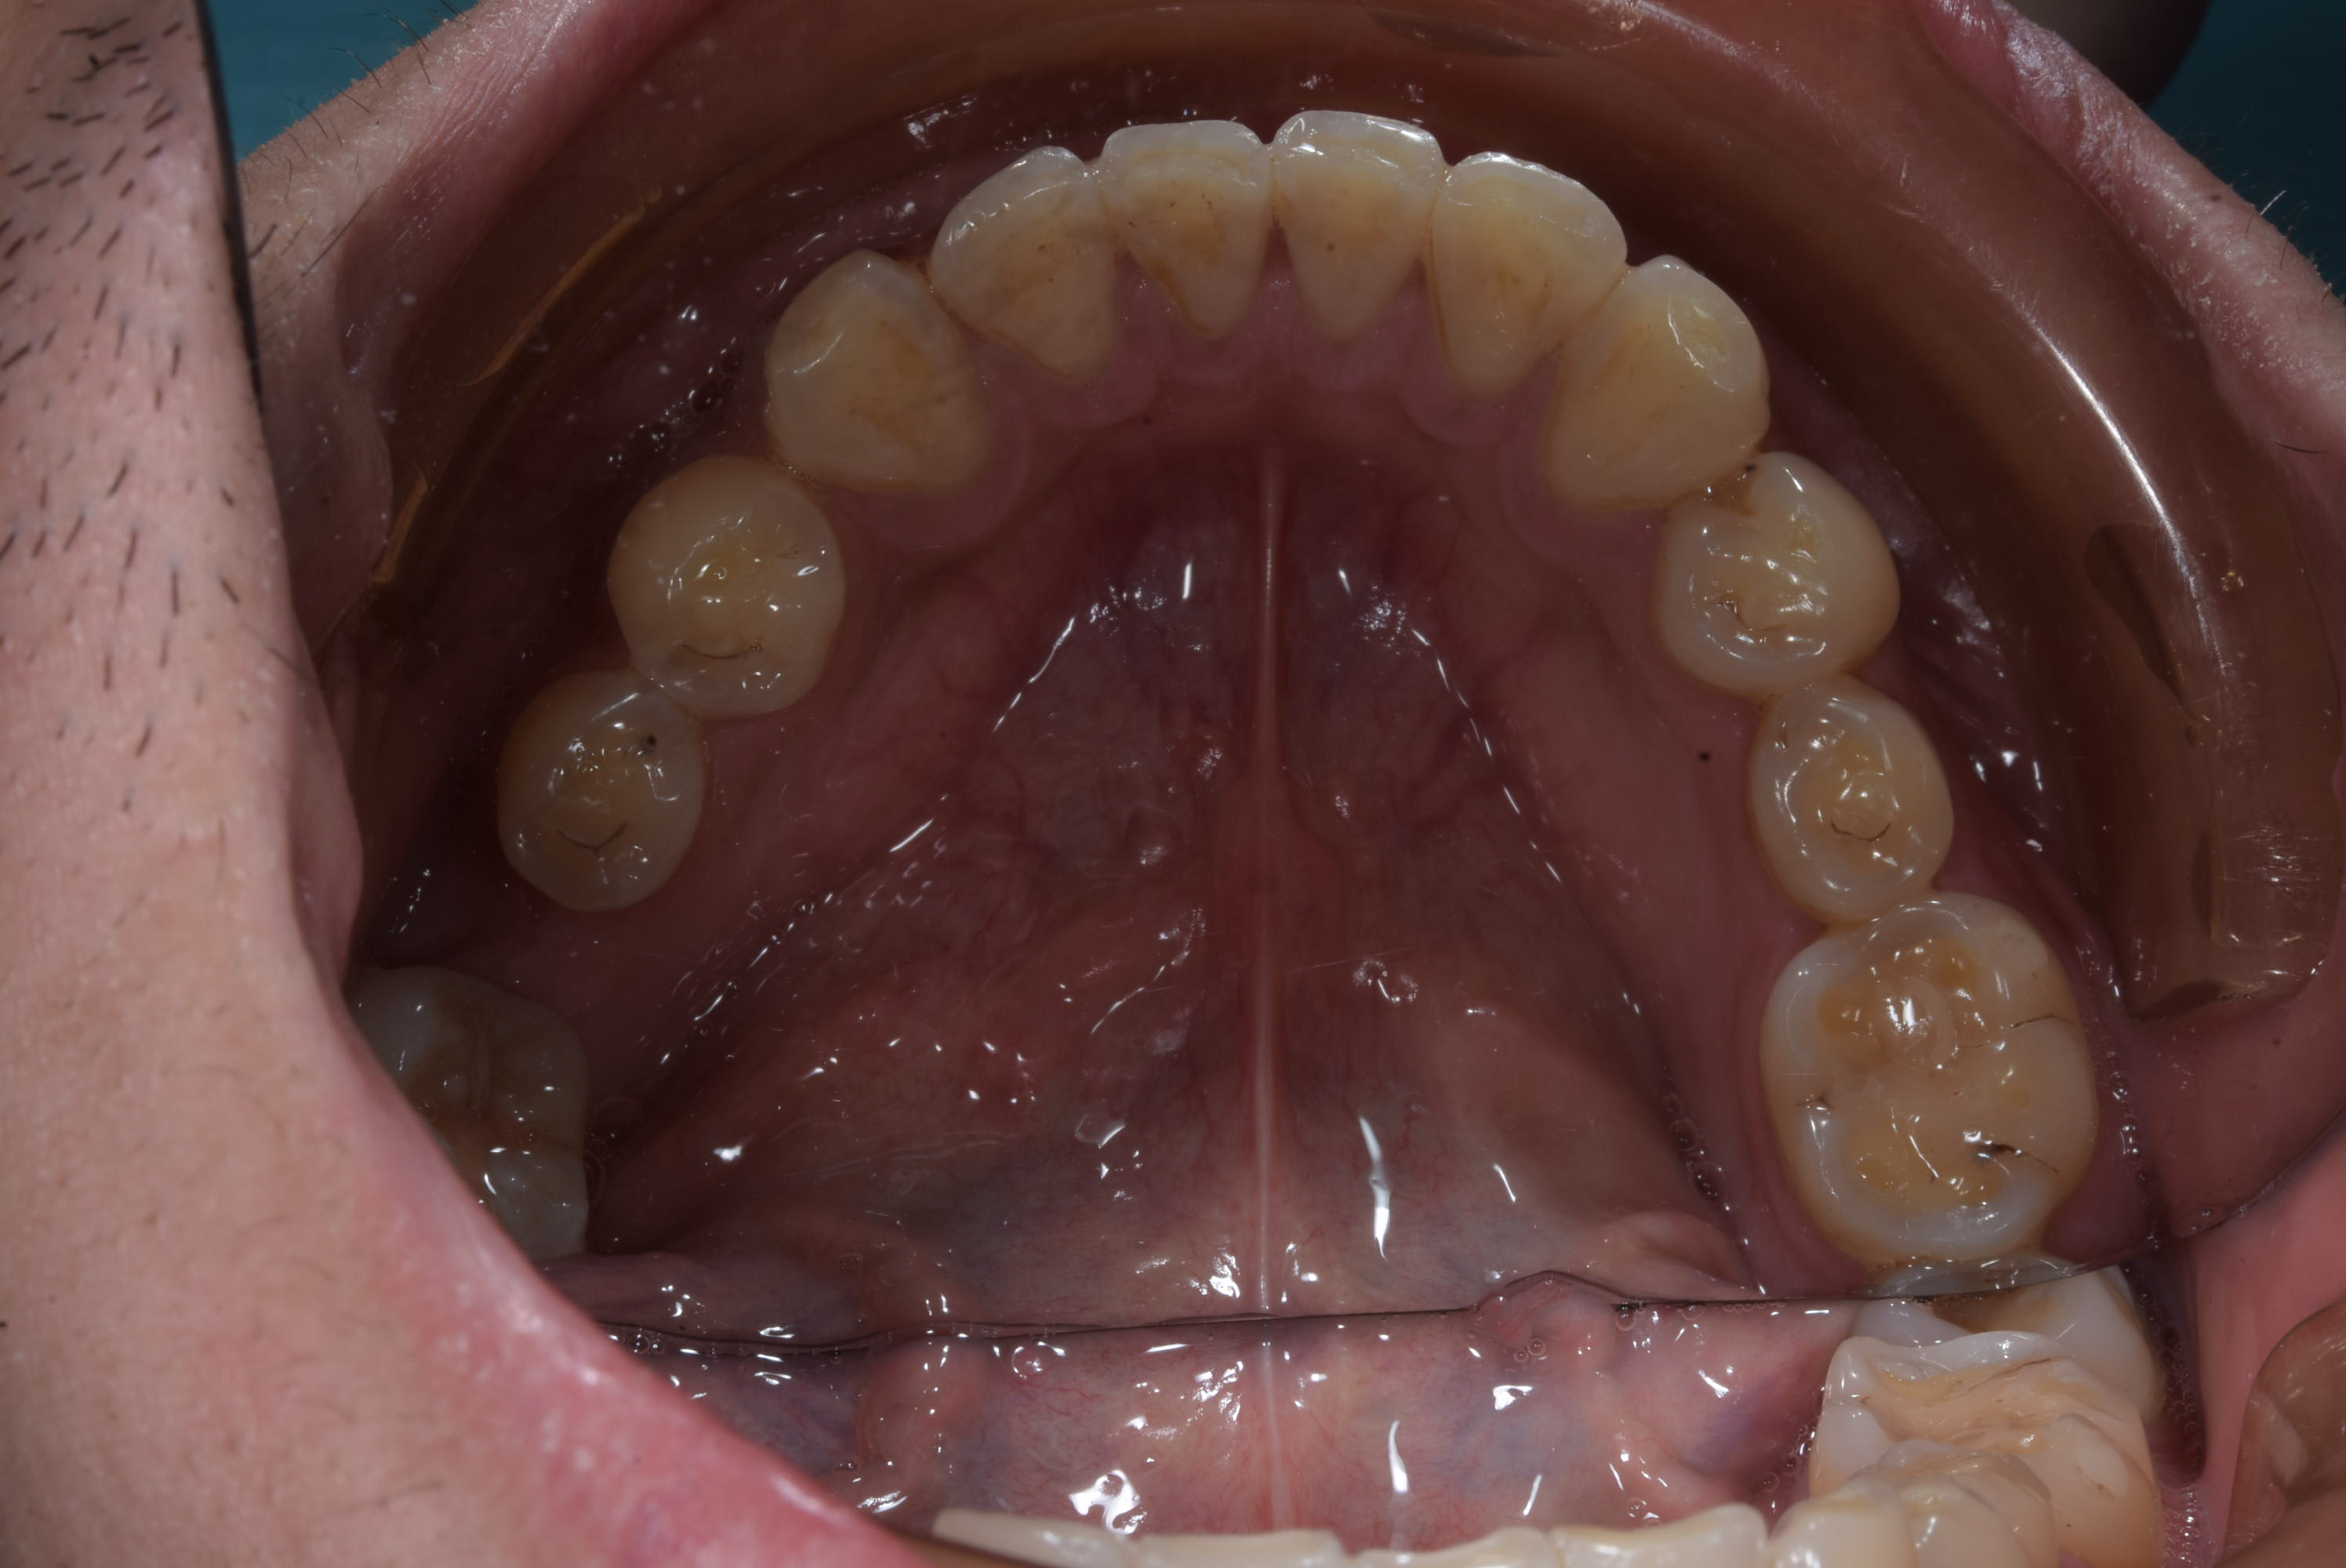

- Prendre une empreinte alignate ( ou utiliser les modéles d'étude )

- Plier un file SS 0.02 en lingual de 45 à 33

- le fixer comme une barre de contention

- mettre un bracket sur 44 et 47

- commencer à aligner la 47 avec un file Niti.

Le file est SS 0.02 et vue que je plie mois même mes contention fixe ( en niti maintenant ) le pliage m'a prie 4 minute. J'ai collé sur le modéle en plâtre 2 minutes puis en bouche :-) . Poser les bracket m'a prit plus de temps.